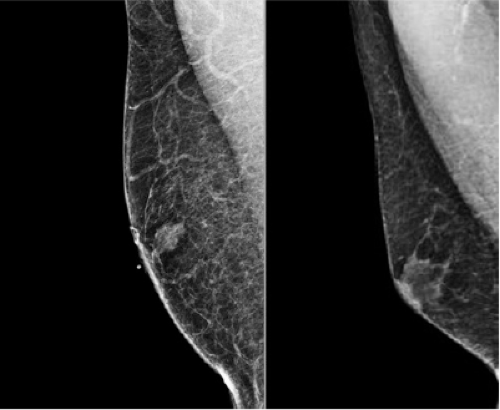

Radiologic workup of the male breast for a palpable mass or clinical finding begins with a diagnostic mammogram (7). A bilateral mammogram is extremely useful. Even if symptoms are unilateral, having the opposite side as a comparison is helpful in making diagnosis and deciding if Ultra Sound (US) is appropriate. The finding is often gynecomastia, which can be bilateral or unilateral. Gynecomastia, proliferation of ducts and stroma, is the most common abnormality in the male breast. There are three main imaging patterns of gynecomastia (nodular, dendritic and diffuse glandular). It is classically described as flame shaped and should have indistinct borders, existing in harmony with surrounding tissue. The most important thing to remember about gynecomastia is that it must be subareolar. From an imaging perspective, differentiating a malignancy from gynecomastia in the subareolar region relies upon evaluation of the borders (Fig. 19-2). Malignancies often have convex borders, however when the borders are spiculated, this can cause some confusion and mimic gynecomastia. Even though male breast cancers most commonly occur in the subareolar location, they can be located anywhere. Any mass in the male breast that is not subareolar is not gynecomastia, and will require additional action (8).

If the appearance is classic “flame shaped” on mammogram and there is NO evidence of a mass, then US should be avoided as this will usually lead to an unnecessary biopsy. US is indicated if the mammogram demonstrates a visible mass or the palpable breast mass is located away from the nipple (Fig. 19-3). Figure 19-4 demonstrates a left subareolar mass with convex borders and coarse calcifications on mammography. Calcifications seen on mammography deserve workup in the male breast. Magnification views should be performed to determine extent and